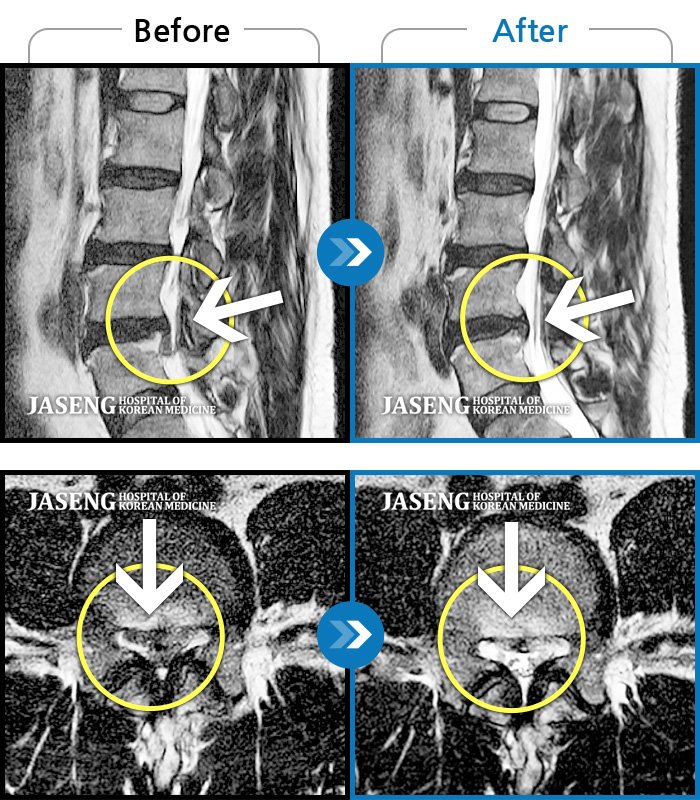

허리디스크

천안 · 김세정 원장

직업 상 무거운 물건을 많이 드는 편으로 6개월간 허리와 둔부의 통증이 지속되었으나 내원 2주 전부터 야간통증까지 동반되어 내원하였습니다.

촬영시기

2022.05.27 ~ 2024.11.02